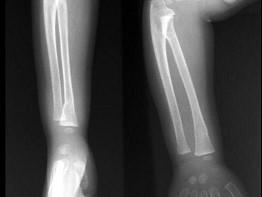

出生6个月的男婴,摔地后右手红肿,结合CR片,正确的骨折类型是?(?)A.青枝骨折B.横行骨折C.斜行骨折D.粉碎性骨折E.压缩骨折

问题 出生6个月的男婴,摔地后右手红肿,结合CR片,正确的骨折类型是?(?)

选项 A.青枝骨折 B.横行骨折 C.斜行骨折 D.粉碎性骨折 E.压缩骨折

答案 A